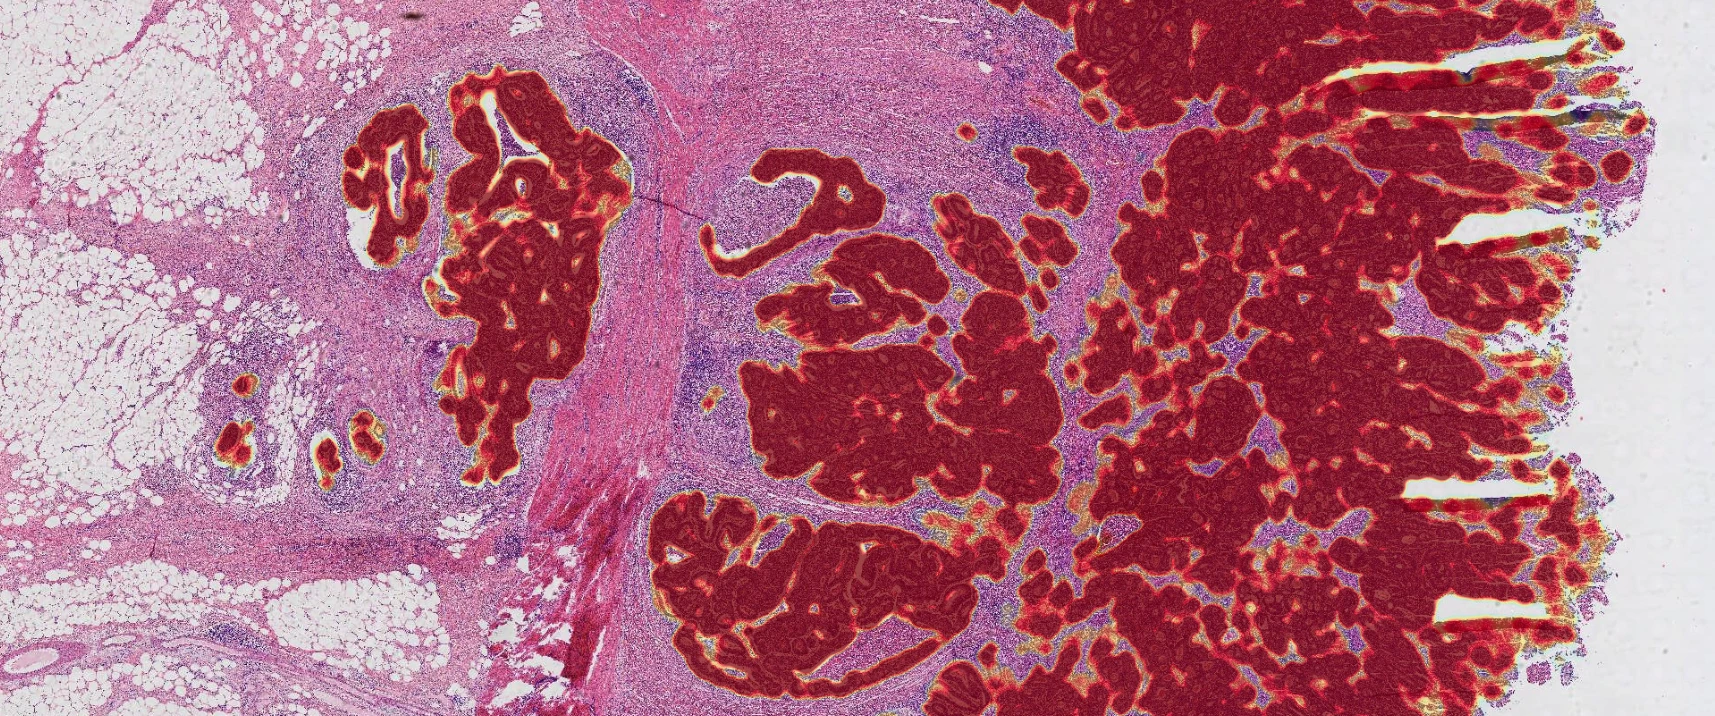

D-PathAI HE Clinical Assistance

Clinical Pathology

Transform diagnostic workflows with AI-powered analysis. Our clinical solutions improve diagnostic accuracy, reduce turnaround times, and enhance patient outcomes across multiple pathology specialties.

Deep Learning Analysis